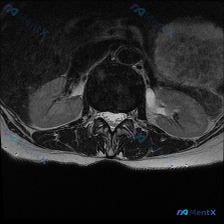

用户提供了一张腰椎MRI T2序列轴位图像,核心问题是评估是否存在椎间盘病变。

- 层面定位:这个层面其实是上腰椎(大概L2或L3椎体水平),不是我们常规看腰椎间盘的L4/5、L5/S1层面,图像里还能看到双侧肾脏下极结构

- 腰椎与椎间盘相关观察:椎管内硬膜囊信号均匀,没有明显狭窄或受压变形,椎体形态完整,这一层面没有看到明确的椎间盘突出、膨出等病变征象

- 意外发现:图像右侧(对应患者左侧肾脏)可见一个边界清晰的局灶性高信号影,信号比周围肾实质更亮,T2序列上这类高信号通常提示液体成分